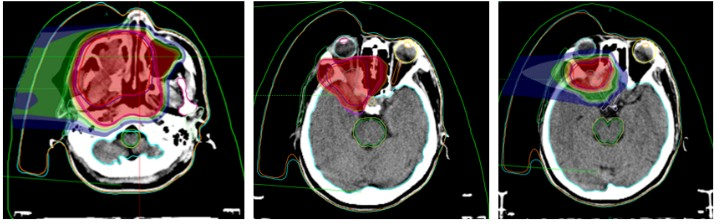

Fabrication of Immobilization Devices for Heavy Ion Therapy

Surface Markers (for Radiotherapy)

Localization CT Scan

Heavy Ion Radiotherapy Target Field Orientation and Dose Distribution